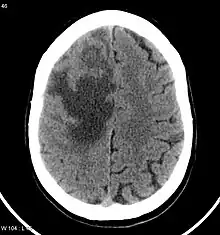

Brain CT scan showing CNS metastasis from the breast, the primary source.

CNS metastases are diagnosed through imaging techniques that produce detailed images of the inside of the body, including parts such as the bones, organs, muscles, and nerves.[13] Magnetic resonance imaging (MRI) and computed tomography (CT) are two representative imaging procedures for this purpose.[12]

MRI scans use strong magnetic fields and radio waves to create an image, while CT scans use X-rays. MRI scans produce more detailed images of bodily structures, particularly soft tissues including the brain,[13] and are better at detecting CNS metastases than CT scans. However, CT scans are sometimes used for the initial imaging modality due to their lower cost and efficiency in screening for multiple conditions.[14]